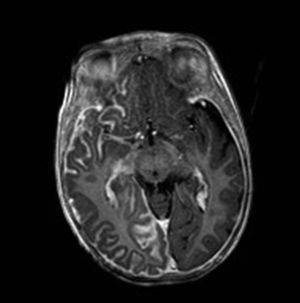

Resonancia magnética cerebralLa RM cerebral con gadolinio es la técnica de imagen de elección para el diagnóstico del SSW28. Con esta técnica es posible visualizar la malformación vascular leptomeníngea que confirma el diagnóstico del SSW (fig. 7). Las calcificaciones en la RM también se pueden detectar en secuencias T2 como imágenes de hiposeñal cortical o yuxtacortical. La resonancia permite además demostrar un drenaje venoso anómalo, una reducción del volumen cerebral, un agrandamiento del plexo coroideo ipsilateral, prominencia de las venas subependimarias y medulares, pérdida de volumen del hemisferio cerebral efecto y una mielinización acelerada subyacente al angioma leptomeníngeo14,24,37. Estos cambios son más evidentes después del año de edad38.